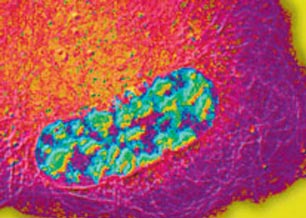

Neurons are highly dependent on an efficient and finely tuned transport system for the delivery of organelles as well as structural and signalling proteins into the axons and for transporting neurotrophic factors from the axon termini to the cell body. The major components of this transport system are a group of specialized motor proteins plus the cytoskeletal networks of microtubules and actin filaments. Motor proteins use these networks as intracellular tracks for transporting their cargos.

Defects in axonal transport have been implicated in the pathogenesis of several neurodegenerative diseases including motor neuron disease. Mutations in the molecular motors dynein and kinesins and several proteins associated with the membranes of intracellular vesicles that undergo transport cause motor neuron degeneration in humans and mice. My laboratory uses a number of mouse models and motor neurons differentiated from induced pluripotent stem (iPS) cells to elucidate the molecular mechanisms of the role of defective axonal transport in the pathogenesis of motor neuron disease.